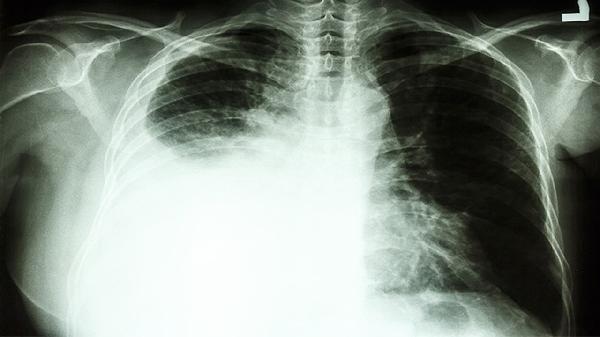

目前关于复方万年青胶囊治疗晚期肺癌的高质量临床研究证据有限,其确切疗效尚需更多循证医学数据支持。个别患者可能出现胃肠道不适等不良反应,用药期间应密切观察身体反应。晚期肺癌病情复杂多变,任何用药都需严格遵循肿瘤专科医生的治疗方案。